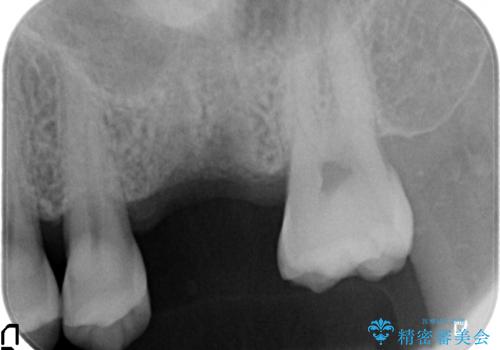

- 歯が割れてしまい、抜歯後のインプラント治療を希望され相談来院されました。

歯が割れるほどの咬合力が強い方でしたので、3本の歯を2本で支えるブリッジではなく、咬合負担能力の増えるインプラント治療にメリットが大きいと言えます。